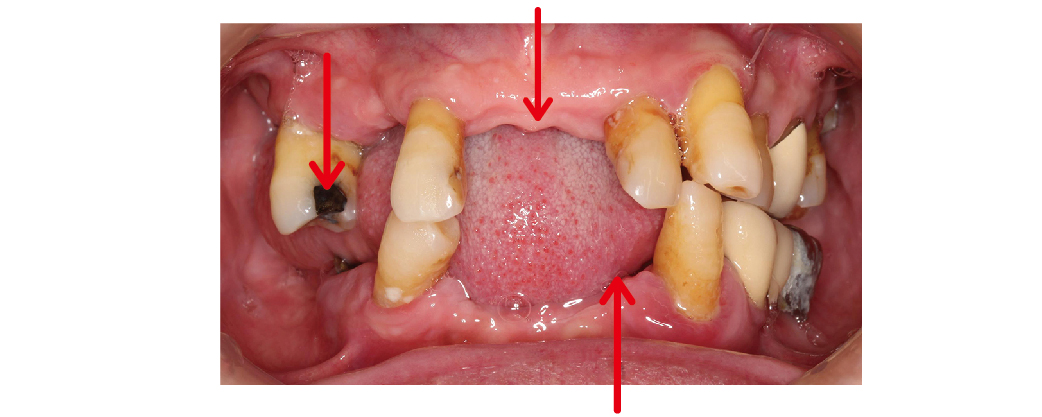

治療流程大致上會分成幾個步驟。首先,我們會幫您做完整的評估,包括拍 X 光、3D 電腦斷層、口內數位照片,確認骨頭的狀況和適合的位置。

▲箭頭處為長期使用活動假牙,造成咬合不便、牙齒鬆動